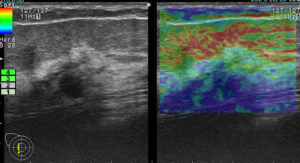

上に挙げた4つのエラストグラフィー

これが何を物語っているか?

エラストグラフィーは何か所見があった際に「これは怪しい!」と思わない限り追加で行わないものです。

これを実は4回も(昨年)行っていたのです。

つまり、(昨年も)その技師は「明らかに癌を疑っていた。」

この4枚のエラストグラフィーは技師の「これは怪しい所見です!是非要精査にしてください!」という心の叫びと言えるんだね!

まさに、その通り!

ただ、悲しいかな。技師さんのその「必死な思い」は、検診画像評価を行う医師には伝わらなかった。

結局、検診結果を出すのは(その画像を見て判断する)医師なのです!

正に診断の問題点1「画像評価」の過ちがここにありました。